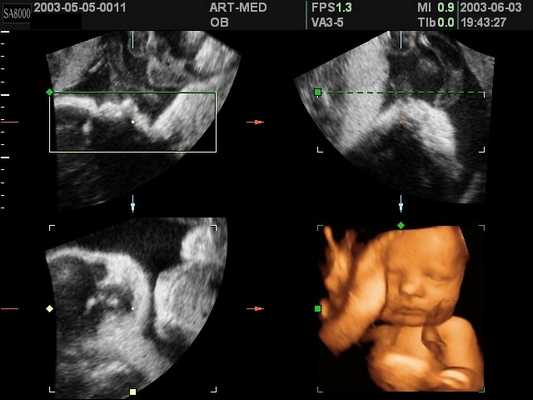

Плод, 3D

[EN] Эхограмма №132: Плод - фронтальная, сагитальная и коронарная плоскости, 3D режим.

Изображение получено с помощью УЗ сканера SonoAce-8000 (снят с производства).